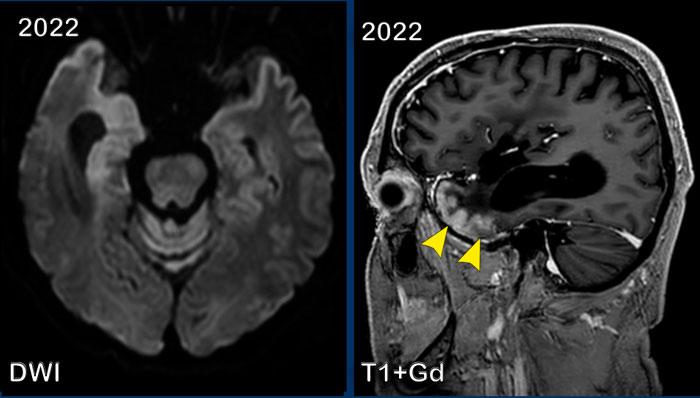

Các hình ảnh này của một bệnh nhân nam 59 tuổi, đã được phẫu thuật cắt bỏ một phần u thần kinh đệm (glioma) vào năm 2008.

Năm 2016, khối u tiến triển và được điều trị bằng xạ trị kết hợp hóa trị.

Năm 2021, không còn dấu hiệu u tồn dư và đến năm 2022, bệnh nhân xuất hiện triệu chứng migraine.

Hình ảnh

Năm 2008, khối u được phát hiện là tổn thương tăng tín hiệu trên chuỗi xung T2W tại vùng hạch nền và thùy đảo bên phải.

Năm 2021, hình ảnh ổn định, nhưng đến năm 2022 xuất hiện ngấm thuốc dạng hồi não ở chất xám thùy thái dương (đầu mũi tên).

Tiếp tục xem thêm hai hình ảnh của bệnh nhân này…

Chuỗi xung DWI cho thấy hạn chế khuếch tán vỏ não ở thùy thái dương phải.

Hình ảnh T1W+Gd theo mặt phẳng đứng dọc ở mức khác cũng cho thấy kiểu ngấm thuốc dạng hồi não.

Đây được gọi là hội chứng SMART (Cơn Đột Quỵ Giống Migraine Sau Xạ Trị – Stroke-like Migraine Attacks after Radiation Therapy).

Đây là một biến chứng muộn hiếm gặp của xạ trị não, đặc trưng bởi phù nề vỏ não và ngấm thuốc dạng hồi não.

Bệnh nhân thường biểu hiện với triệu chứng migraine, nhưng cũng có thể có co giật và liệt nửa người.

Trong bối cảnh có tiền sử xạ trị não, cần nghĩ đến hội chứng SMART.

Chẩn đoán kịp thời là cần thiết để tránh các thủ thuật xâm lấn không cần thiết.

Đây là bệnh tự giới hạn.

Đây là chẩn đoán loại trừ và cần phải loại trừ thiếu máu cục bộ, PRES và co giật.